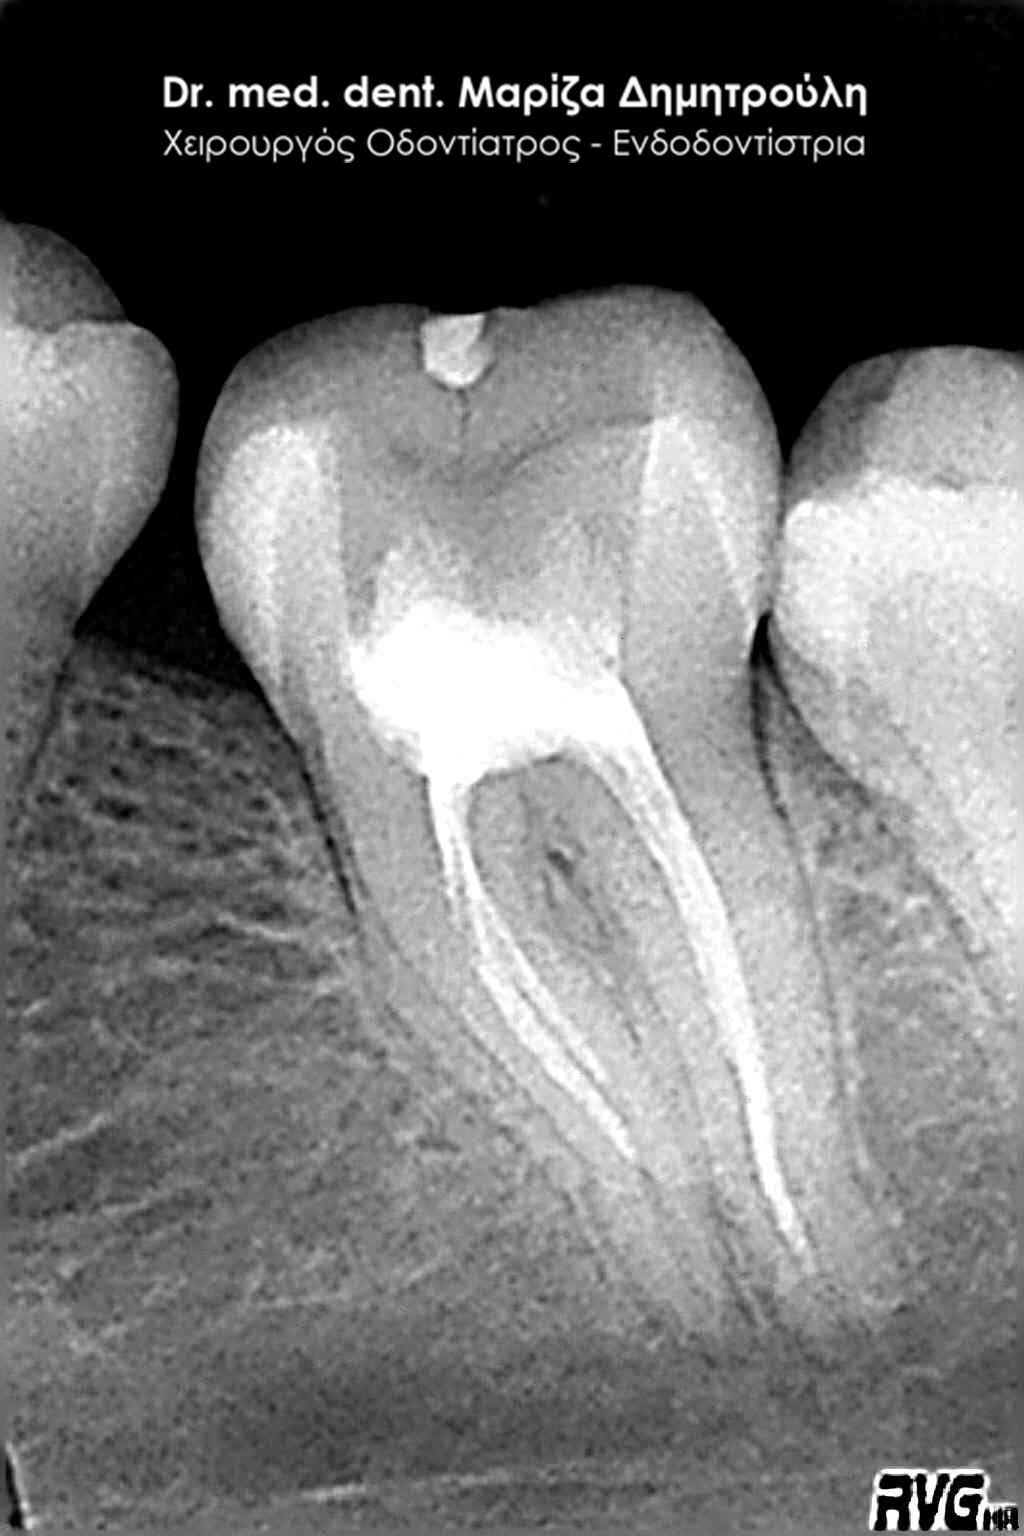

Η ασθενής προσήλθε με έντονο πόνο στο ιατρείο και είχε λάβει τις προηγούμενες μέρες αντιβίωση, εφόσον στην άνω αριστερή πλευρά της είχε οίδημα. Μετά την κλινική εξέταση διαπιστώθηκε η ύπαρξη ενός συριγγίου υπερώια μεταξύ των δύο άνω αριστερών γομφίων. Πραγματοποιήθηκε ακτινογραφία με την τοποθέτηση ενός κώνου γουταπέρκας για τη διάγνωση του υπαίτιου δοντιού, που είχε προκαλέσει την εμφάνιση του συριγγίου. Σύμφωνα με όσα αποκάλυψαν η κλινική και ακτινογραφική εξέταση ακολούθησε η έναρξη απονεύρωσης στο δεύτερο άνω αριστερό γομφίο, δεδομένου οτι είχε ένα βαθύ λευκό σφράγισμα ρητίνης που εκτεινόταν στο ύψος του νεύρου του δοντιού. Το δόντι είχε έντονα συμπτώματα πόνου κατά την επίκρουσή του.

Μετά την ολοκλήρωση της απονεύρωσης στο δεύτερο άνω αριστερό γομφίο το δόντι είναι ασυμπτωματικό. Η αποκατάσταση του δοντιού πραγματοποιήθηκε με λευκό σφράγισμα ρητίνης, εφόσον το έλλειμμα των οδοντικών ιστών ήταν μικρό και δε χρειαζόταν η προστασία του δοντιού με θήκη / στεφάνη δοντιού.

Σε δεύτερη φάση θα ακολουθήσει η επανάληψη απονεύρωσης στον πρώτο άνω αριστερό γομφίο, καθώς η απονεύρωση του δεν καλύπτει όλο το μήκος των ριζών του δοντιού και το δόντι μετά το πέρας της ενδοδοντικής θεραπείας συνεχίζει να πονά.

Εικόνα του δοντιού μετά τη διάνοιξή του και την επεξεργασία των ριζικών σωλήνων του δοντιού

Κλινική εικόνα του δοντιού με το υλικό έμφραξης στους ριζικούς σωλήνες του

Αποκατάσταση του δοντιού με λευκό σφράγισμα ρητίνης